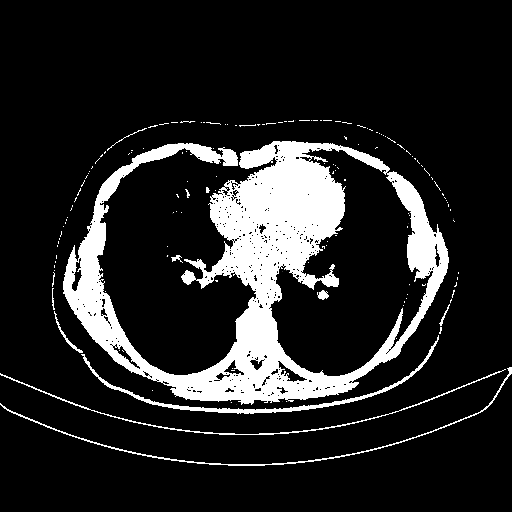

Original NATIVE CT scan (input)

Full window (WL 1023.5, WW 4095 β†’ Low βˆ’1024, High +3071)

Actual HU range: [-1024.0, 3071.0]